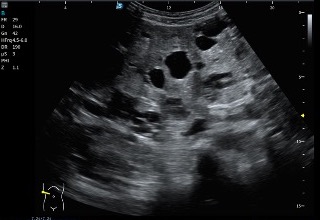

Como parte de la misma exploración del protocolo de ecografía abdominal, se procede al estudio de ambos riñones.

En ellos se detectan:

- Múltiples lesiones anecoicas

- Morfología redondeada

- Distribuidas por el parénquima renal de ambos riñones